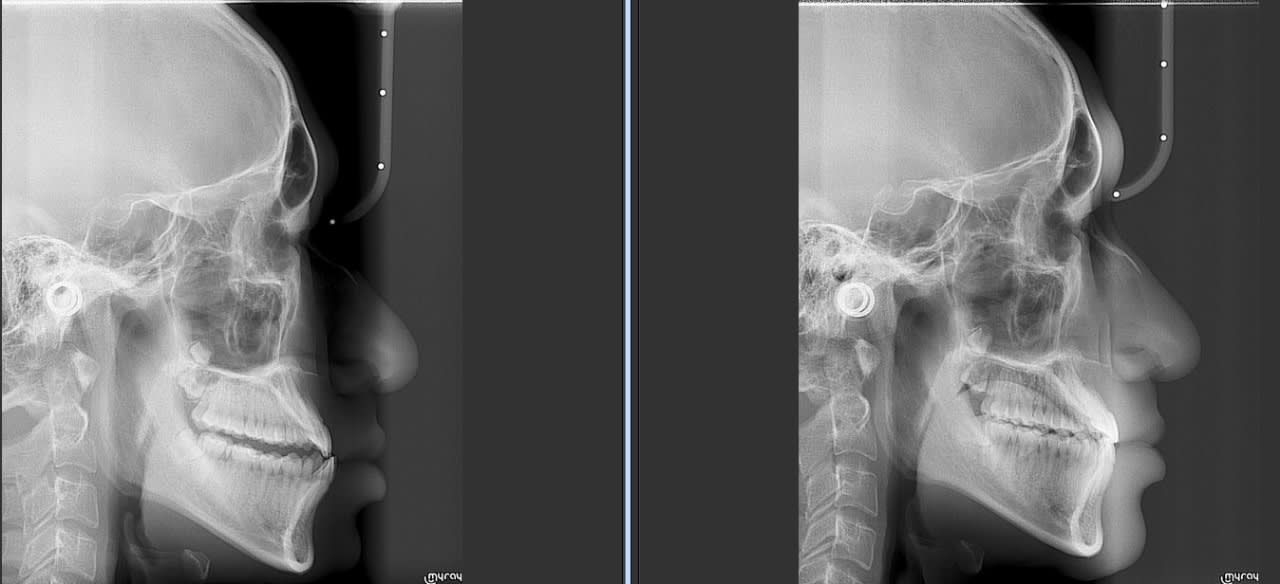

Un cas plus inhabituel Patient class III avec cross bite antérieur. Ici gros espaces en antérieur à la mandible. Vue le coté inhabituel j'ai fait un set up qui m'a indiqué qu'il fallait à la fois mésialer les secteurs postérieur supérieur et inférieure. Traduction pas de mécanique class III classique.

Je vois pas trop l’interet Pour le cross bite antérieur d’autant que sur la télé , tes inc Sup se sont vestibulees . Pour moi , c’est un cas chir , sauf si refus du patient alors j’aurais fait une mécanique classique de classe 3 .

Pour ce patient il y a avait des espaces important à la mandibule. Visuellement je trouvais le cas inhabituel donc j'ai fait un set up 3D. Résultat il fallait mesialé à la fois à la mandibule et au maxillaire.

Une mécanique classique de class III était out ici à moins de vouloir faire sortir les incisives de la corticale.

Il y a trop de compensation orthodontique ( proalveolie importante afin de corriger l’articulé Inversé antérieur) .

Les espaces postérieures crée auraient servi à décongestionner la biproalveolie et aussi decompenser la proalveolie sup du un une retromaxillie .

Au vu de la télé , sans chir , j’aurais reculé les inc inf au Max et pas mésiale les secteurs latéraux inf (??)

- comparé l'inclinaison post et durant traitement des incisives il y a eu compensation mais pas de changement majeurs

- le profile est amélioré

Avec tout le respect que je dois à ton travail , Il me semble que sur ta radio , t’as quand même eu un repositionnement incisif inf . Faudrait faire des superpositions pour savoir ce qui s’est vraiment passé mais je ne suis pas sure que tu aies bien mesiale les secteurs lat Inf non plus.

Quelque photo avant après. Les pano sont intéressante car elles montre bien que l'on à mesialé l'ensemble des secteurs post, que sa soit à la mandibule ou au maxillaire.